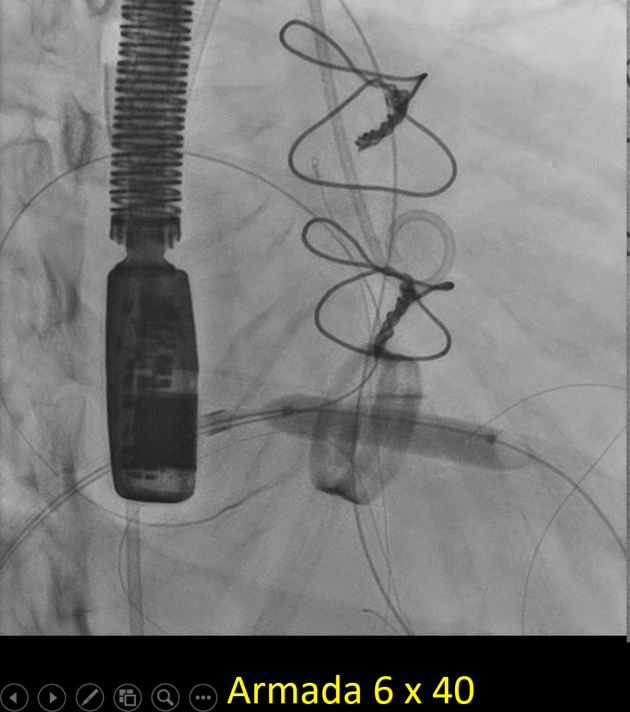

Since TLT was not possible and surgeon refused for emergencyTranscatheter valve disruption was planned. The issues involve in the procedure were 1.Septal Puncture -due to pericardial patch in IAS, alteredanatomy due to Sx & ac dilatation of LA- Angle of puncture and Site ofpuncture. 2 Selection of wire3.Balloon- Size, make ( Compliant Vs NC), 4.Complication-like disc embolization, stuck disc leading to ac severe MA and strud fracture. The septa puncture was done as standard approach, a V18 wirewas parked in PV through a 7f Mullin sheath, Straight Turmo wire was was takenthrough a 6 JR to cross the valve and a 6 x 40 Armada balloon was dilatedacross the disc. Good acute result was obtained. The LA mean decreased from36-40 to 10-12mmHg. Post procedure the inotropic support, O2 demand decreasedover next 12 hr. However after 24 hr pt developed refractory RH failure and persistentanuria requiring SLED. And pt succumbed to the procedure 3 days after theprocedure.